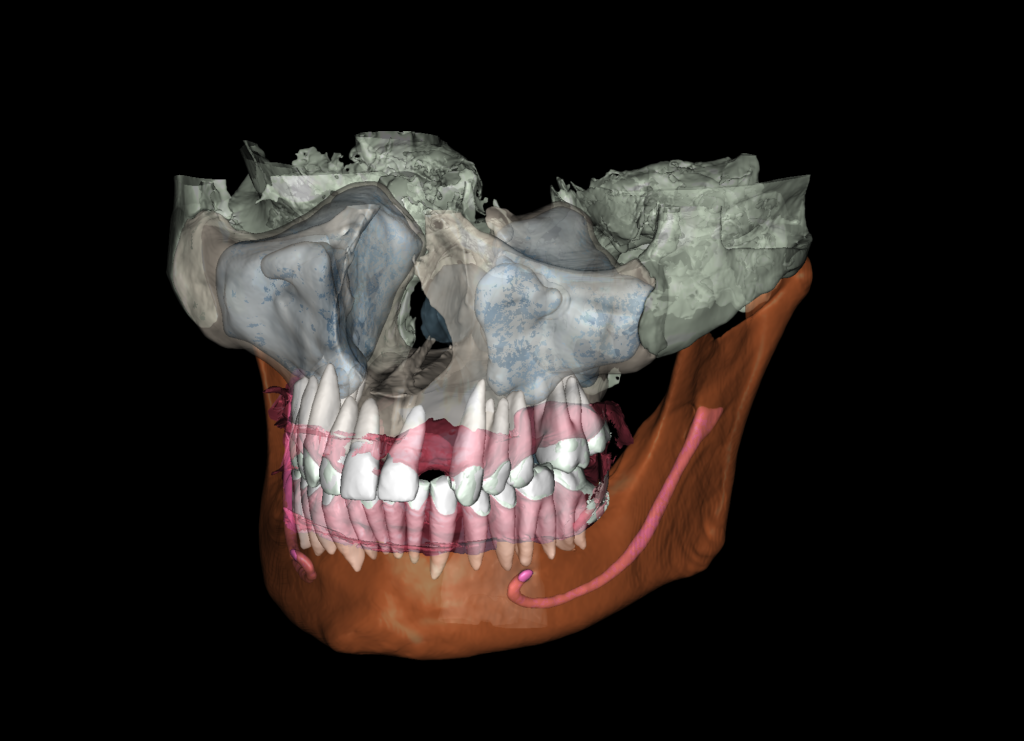

С использованием модуля «3D модели» Diagnocat, возможно создание виртуальных навигационных шаблонов. Для этого в этот модуль загружаются данные из интраорального сканирования и подбирается соответствующая КЛКТ для их совмещения